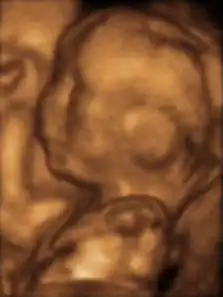

18 недель после зачатия[12]

- Трёхмерное УЗИ 12-недельного плода

Плод на 17-й неделе

Плод на 20-й неделе